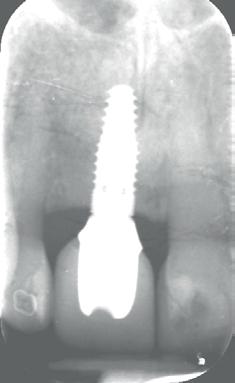

Een 47-jarige collega presenteert zich in onze verwijspraktijk voor endodontie. Hij heeft enige tijd geleden zijn kroon op de 11 laten vervangen (afbeelding 1). Omdat er geen klinische en röntgenologische aanwijzingen waren voor een periapicale laesie of een insufficiënte wortelkanaalbehandeling van de 11, werd besloten de endo, die dateerde van meer dan 30 jaar geleden, niet te reviseren (afbeelding 2). Tijdens een routinematige gebitsreiniging constateert zijn mondhygiënist een pocket van 7 mm aan de mesiopalatinale zijde van 11 (afbeelding 3). De nieuwe kroon wordt tijdelijk gecementeerd, en omdat

1: Klinische foto van bovenfront

2: Röntgenfoto van 11 met zilverstift sectie

3: Pocket palatinaal 11

4: Horizontale doorsnede CBCT met radiolucentie mesiopalatinaal van de 11

de patiënt zich zorgen maakt over deze toevalsbevinding, wil hij de 11 laten beoordelen door een endodontoloog.

Er wordt een CBCT gemaakt die een laesie aan de mesiopalatinale zijde van 11 laat zien (afbeelding 4).